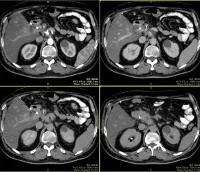

МРТ брюшной полости. Современный метод диагностики, основанный на явлении ядерного магнитного резонанса и применяемый с целью определения патологических изменений во внутренних органах. С помощью процедуры удается визуализировать полые и паренхиматозные структуры: печень, почки, поджелудочную железу, селезенку, пищеварительный канал. В ходе МРТ брюшной полости возможна оценка состояния кровеносных и лимфатических сосудов, расположенных в данной анатомической зоне. Исследование позволяет диагностировать дегенеративные, воспалительные и опухолевые процессы, определять перемещение физиологических жидкостей, выявлять травматические повреждения. МРТ брюшной полости является неинвазивным методом диагностики, может осуществляться нативно или с использованием контраста.

Магнитно-резонансная томография брюшной полости использовалась в медицине в течение относительно короткого времени - с 1980-х годов, за это время, метод был признан одним из наиболее информативных и безопасных для здоровья пациента. В исследовании используются электромагнитные волны определенной частоты, которые взаимодействуют с атомами водорода, расположенными в клетках человеческого организма. Во время магнитно-резонансной томографии брюшной полости специалист получает несколько изображений исследуемого органа в разных проекциях и плоскостях. Это позволяет построить трехмерную модель исследуемой области, определить характеристики анатомического строения органов, оценить размеры, структуру и другие характеристики патологических очагов, диагностировать заболевания даже на ранних стадиях развития, еще до симптомы.

Безопасность техники позволяет сканировать даже детям и беременным женщинам (начиная со второго триместра). МРТ брюшной полости имеет клиническое значение для таких областей практической медицины, как гастроэнтерология, абдоминальная хирургия, сосудистая хирургия, ангиология. МРТ брюшной полости также довольно популярна в онкологии, поскольку показывает точное местоположение опухоли, ее размер и степень распространения в различных анатомических структурах. Использование контрастного вещества позволяет четко визуализировать сосуды, выявить участки нарушения кровотока и лимфотока, воспалительные изменения.